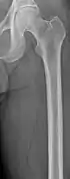

The diagnostic examination of a person with suspected multiple myeloma typically includes a skeletal survey. This is a series of X-rays of the skull, axial skeleton, and proximal long bones. Myeloma activity sometimes appears as "lytic lesions" (with local disappearance of normal bone due to resorption). And on the skull X-ray as "punched-out lesions" (pepper-pot skull). Lesions may also be sclerotic, which is seen as radiodense.[47] Overall, the radiodensity of myeloma is between −30 and 120 Hounsfield units (HU).[48] Magnetic resonance imaging is more sensitive than simple X-rays in the detection of lytic lesions, and may supersede a skeletal survey, especially when vertebral disease is suspected. Occasionally, a CT scan is performed to measure the size of soft-tissue plasmacytomas. Bone scans are typically not of any additional value in the workup of people with myeloma (no new bone formation; lytic lesions not well visualized on bone scan).

Multiple myeloma in the upper arm

Femur with multiple myeloma lesions

Same femur before myeloma lesions for comparison